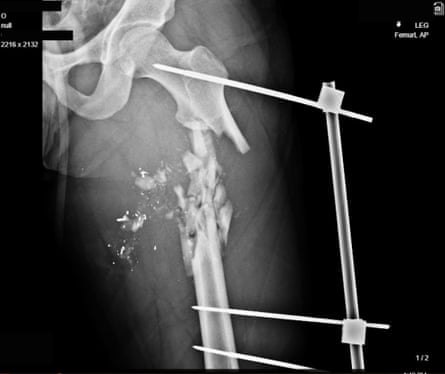

In nine of the patients, the high-calibre bullets are still embedded in the body and clearly visible in the scans. In another seven, the bullet is not visible, but ballistics and medical experts agree that the injuries shown – such as a femur bone shattered along a clear pathway, with metal fragments – are extremely likely to have been caused by a high-velocity bullet. The images showing projectiles have been analysed by two independent ballistics experts, who identify the bullets as full metal jacket rounds consistent with those fired from assault rifles such the AK-47 or KL-133 – weapons used by the IRGC. Full metal jacket bullets often do not deform on impact, holding a clear “bullet” shape. “These are lethal purpose weapons,” says ballistics expert NR Jenzen-Jones, director of Armament Research Services, who has assessed a subset of the images.

In their review of the images, one of the medical analysts describes them as “the kind of injuries you would see in wartime: those are chest shots with a military weapon”. “If you’re firing those kind of weapons at people, you are trying to kill them.”

Haar adds: “These are not the kind of little bullets that we usually see even in policing in the US. These are a whole different level of weapon.”